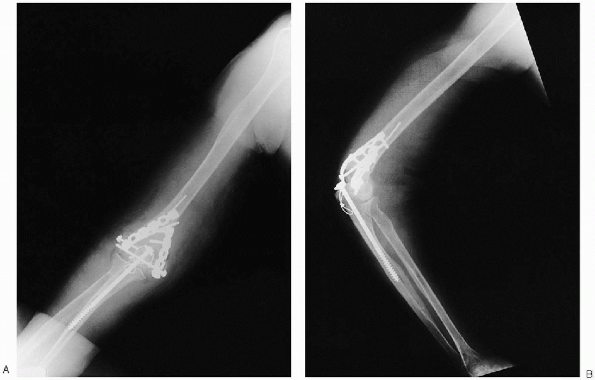

FIGURE 10-25. Final anteroposterior (A) and lateral (B) radiographs.